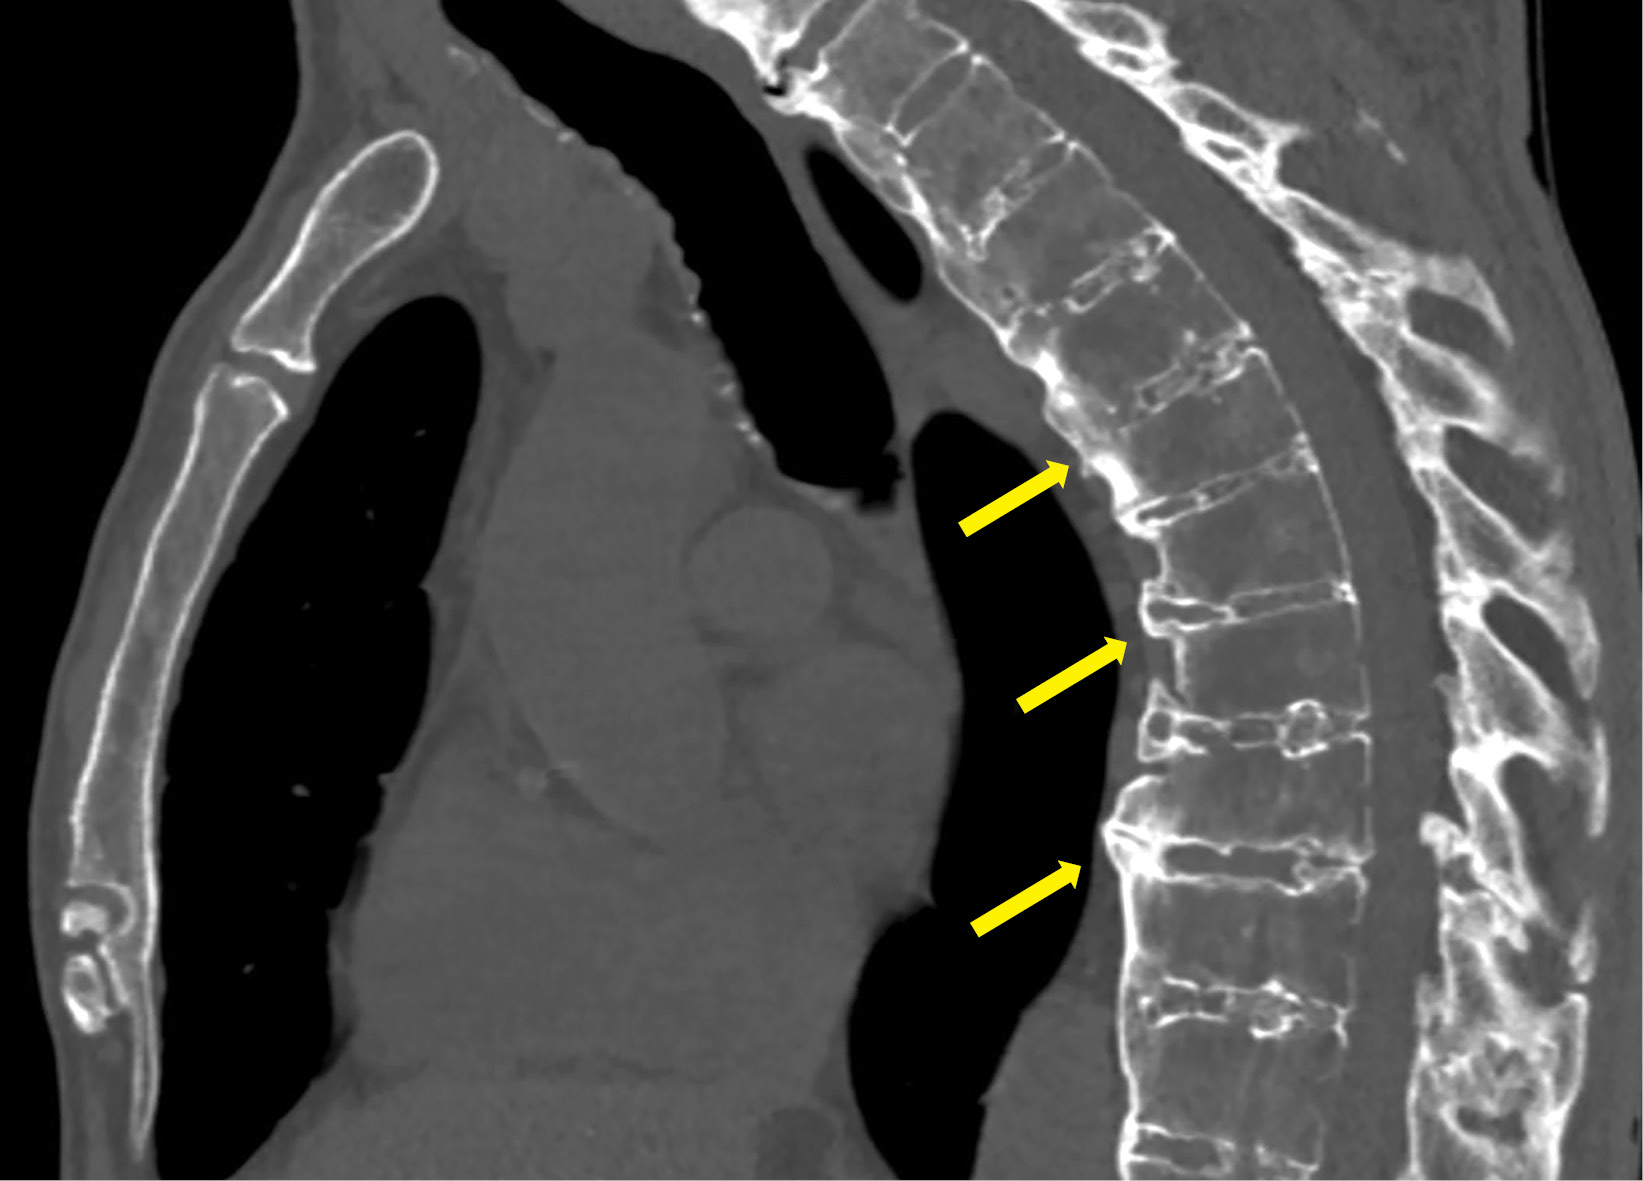

2. Figure 2. Spinal lesions in a patient with acromegaly. | |